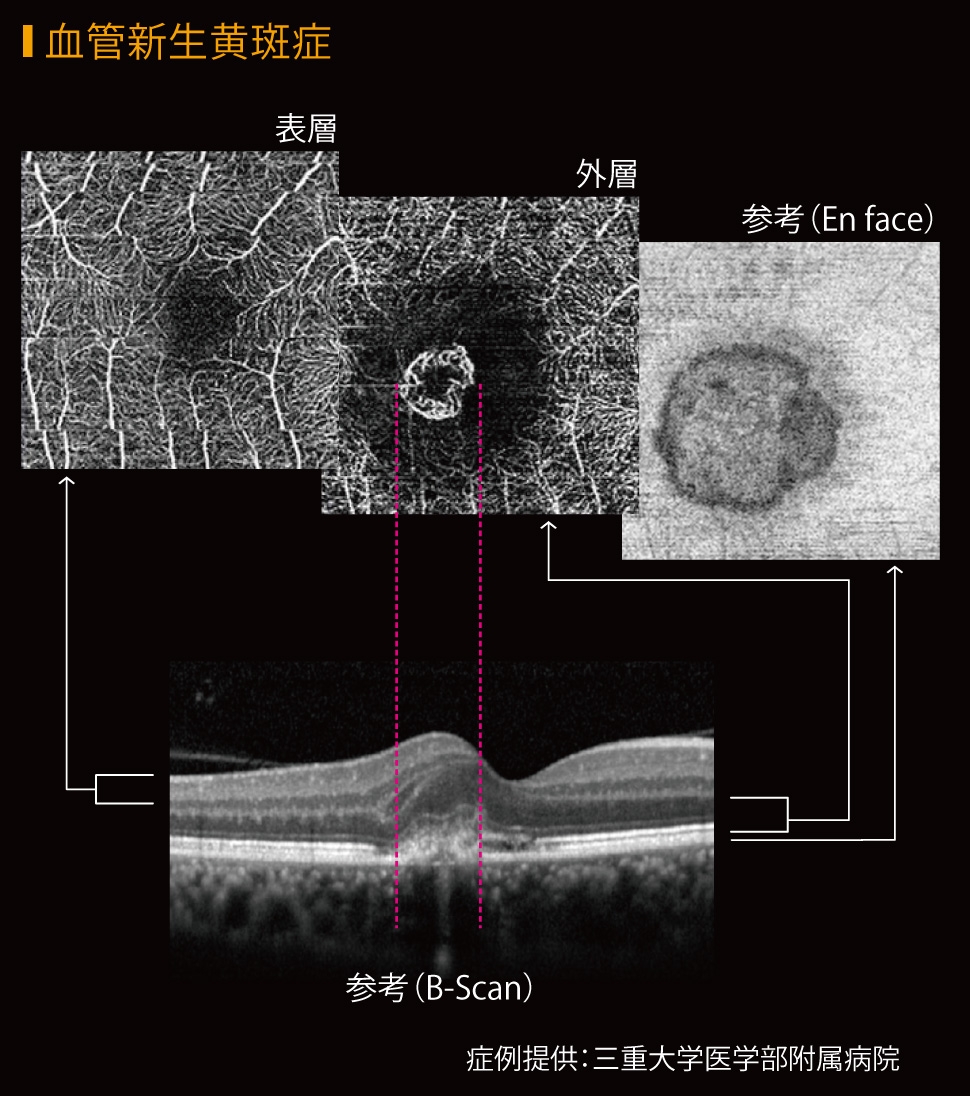

- CT-Angiographyにより、非侵襲で網膜毛細血管を各層別に観察可能(オプション)

任意設定により5種類(初期設定:網膜全層、表層、深層、外層、脈絡膜)のパノラマが同時に自動合成できます。

網膜表層 |

網膜深層 |

網膜外層 |

脈絡膜 |